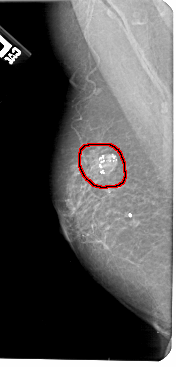

FILE: A_1306_1.LEFT_MLO.OVERLAY

TOTAL_ABNORMALITIES 1

ABNORMALITY 1

LESION_TYPE CALCIFICATION TYPE AMORPHOUS DISTRIBUTION N/A

LESION_TYPE MASS SHAPE OVAL MARGINS CIRCUMSCRIBED

ASSESSMENT 2

SUBTLETY 5

PATHOLOGY BENIGN

TOTAL_OUTLINES 1

BOUNDARY